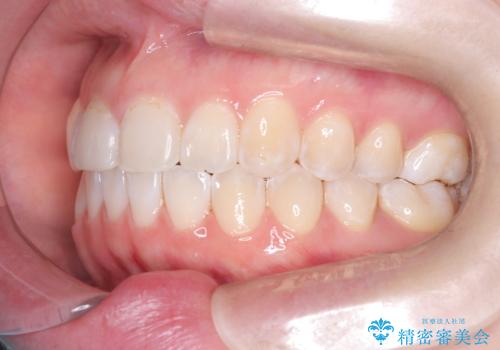

- 他院で矯正治療を受けていた患者様が、より理想的な仕上がりを求めて転院されました。主なお悩みは正中(前歯の中心)がズレていることで、歯並び全体をきれいに整えたいとのご希望でした。治療には舌側(裏側)に装置を装着するフルリンガル矯正を採用し、さらにアンカースクリューを用いて奥歯を後方へ移動(遠心移動)させることでスペースを確保し、正中を調整する計画を立てました。

矯正装置を装着し、アンカースクリューを活用しながら奥歯を少しずつ後ろへ動かし、正中を整えていきました。治療には時間がかかりましたが、計画通りに歯を移動させ、バランスの取れた歯並びへと仕上げることができました。裏側矯正のため、見た目を気にすることなく治療を進められた点も、患者様にとって大きなメリットでした。治療後は、「正中がしっかり合って、口元がスッキリした」とご満足いただきました。